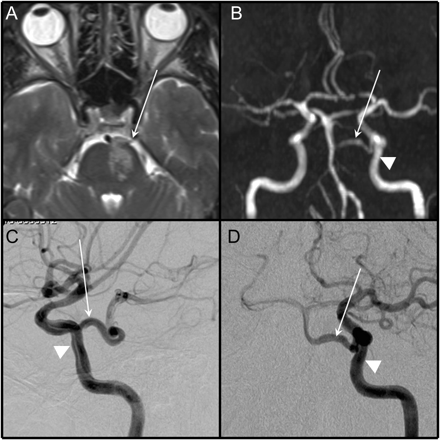

几分钟后与警察发生争执,一个55岁的人开始讲话中提到的困难和右侧的弱点没有头痛和颈部疼痛。构音障碍和右轻偏瘫(4/5)级没有眼扰动被发现。左腹侧hemipontine三叉动脉梗塞从身体的同侧的曲折的原始记录(图)。脑血管造影未能揭示潜在的动脉解剖。

图

白色箭头指向原始三叉动脉(模拟)。MRI、fluid-attenuated反转恢复序列,证明左腹侧脑桥的梗死(A)。磁共振血管造影显示近端hypoplastic-stenotic vertebrobasilar系统(B)选择性左颈内动脉血管造影:横向(C)和前后的视图(D) (B)视角一样。三角箭头指向左侧颈内动脉(罪犯)。